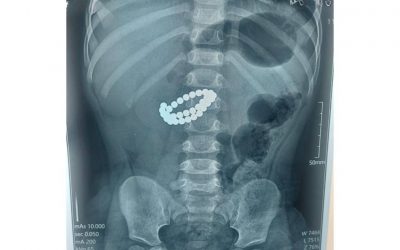

Фото: видеодан скрин Аурухана – үміт сыйлайтын орын еді, бірақ бұл жолы қайғылы оқиғаға айналды. Бұл туралы QazaqToday.info ақпараттық порталы хабарлайды. Ақтаулық 13 жастағы жасөспірімнің өлімі қоғамда үлкен сұрақ туғызды. Туыстарының айтуынша, баланы алғаш тексерген дәрігерлер толық қарамай, үйіне жіберген. Арада уақыт өткенде оның жағдайы күрт нашарлап кеткен. Кейін белгілі болғандай, соқырішегі жарылып, инфекция бүкіл…